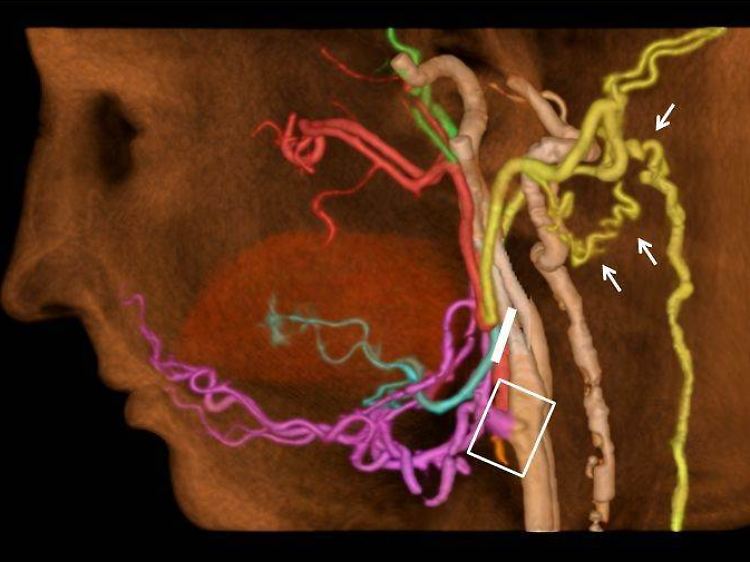

CT-Angiografie nach einer Gesichtstransplantation.

Bei einer Gesichtstransplantation erhalten Menschen mit dramatischen und entstellenden Verletzungen Gewebe von Organspendern. Während der Operation verbinden die Chirurgen die Arterien und Venen des Patienten mit denen des Spendergewebes. Experten hätten bisher angenommen, das Blut fließe bei den Patienten lediglich durch diese Verzweigungen, sagte Rybicki. Nun beobachteten die Mediziner einen Vorgang, den sie Kollateralisation nennen. Dabei verlängern und weiten sich bestehende Blutgefäße und bilden neue Netzwerke untereinander.

Auch Gefäße, die eher mit der Blutversorgung von hinteren Kopfteilen in Zusammenhang gebracht werden, spielten offenbar eine Rolle dabei, wie gut sich die Blutbahnen neu organisierten. Die Forscher folgern, dass vor einer Transplantation auch überprüft werden muss, ob diese Gefäße normal arbeiten. Das Team erhofft sich, Gesichtstransplantationen künftig besser planen zu können. Für die Untersuchungen verwendeten die Radiologen eine computertomographische Methode, mit der die Gefäßdurchblutung erfasst werden kann.